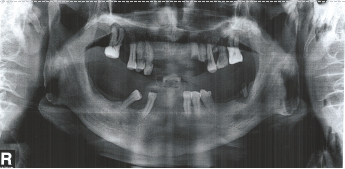

2016年10月20日曲面断层示:口腔内多颗牙齿缺失,分别为右上126、左上12、右下1247、左下1267,其中双侧上下切牙牙槽骨隐见牙槽窝,片中所示牙槽骨吸收明显,遗留牙齿的牙槽骨吸收均达根长的1/2以上。

2016年10月20日曲面断层(纸质图片)